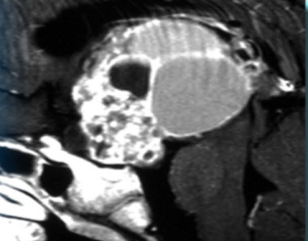

2. Рис.2. Краниофарингиома | |